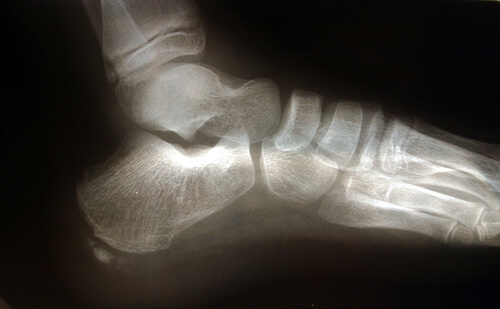

解剖学的に見る足

解剖学的に見ると、足底筋膜とは踵骨と呼ばれるかかとの骨から足裏の前方までに広がる厚さの強い繊維組織帯をいいます。

足のアーチを維持して衝撃を吸収しながら私たちの体のバランスを保つため、歩行時などに重要な役割を果たします。

足底筋膜に、運動など様々な要因で継続的に強い圧力と刺激を継続的に加えることで、微細損傷を継続的に受け、足底筋膜炎を発症します。

扁平足やオーバープロネーションと呼ばれる足底筋膜が内側に傾きがちな場合は、組織への過剰は圧力により損傷が起こりやすく、足底筋膜炎を発症するリスクが高まります。